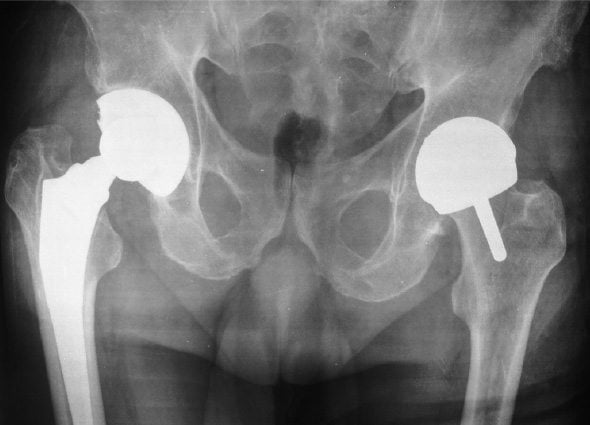

Хирургическое вмешательство, в ходе которого врач удаляет изъеденный артритом участок бедренного сустава, заменяя его искусственным имплантатом, состоящим из пластиковых и металлических комплектующих, называют эндопротезированием. Операция дает продолжительный терапевтический эффект и показана, если консервативные методы лечения не облегчают состояние больного.

Успехом заканчивается примерно 95-98% операций по эндопротезированию тазобедренного сустава. Однако риск осложнений, как и при других видах хирургических вмешательств, все же присутствует.

- вывих и ослабление бедренного соединения. Вывихнутый сустав ставится на место под наркозом;

- износ сустава. Как и естественный сустав, протез изнашивается. Увеличивают этот риск игнорирование предписаний врача, отсутствие физической активности, лишний вес и другие факторы. Керамические и металлические имплантаты менее подвержены истиранию;